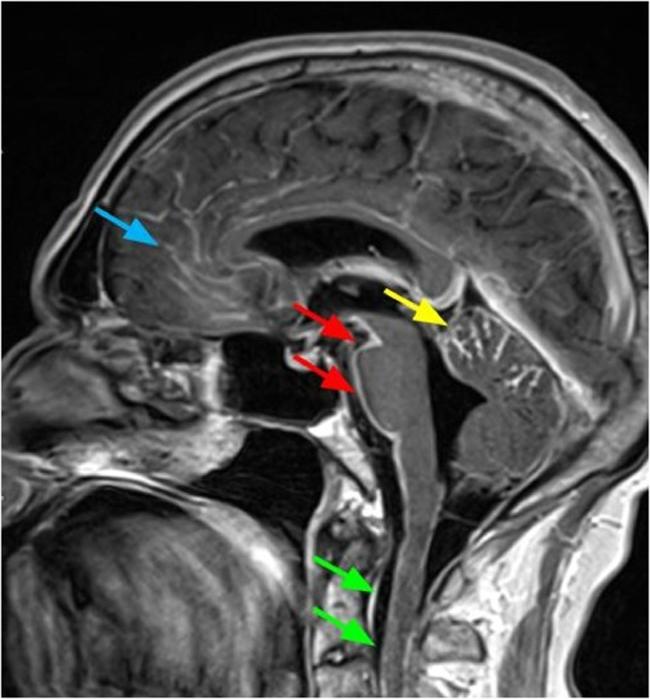

家族性软脑膜淀粉样变性的颅内和全身表现,CT和MRI所见

Leptomeningeal amyloidosis is a subset of familial transthyretin amyloidosis, a family of diseases occurring in conjunction with multiple known mutations of the transthyretin gene. Though this is primarily a disease of the central nervous system, amyloid deposition is multisystemic. We describe a case of a 61-year-old man with known central nervous system amyloidosis presenting to the emergency room with stroke-like symptoms, including left hemineglect, right gaze paresis, and left hemiplegia, atop baseline dementia. A noncontrast CT head demonstrated ventriculomegaly and no acute hemorrhage. Urinalysis indicated an underlying urinary tract infection, ultimately believed to have prompted a breakthrough seizure. Electroencephalogram revealed diffuse encephalopathy. Contrast-enhanced MRI demonstrated hallmarks of intracranial amyloid with no new infarct. Previously taken noncontrast CT neck and thorax demonstrated evidence of systemic disease.

软脑膜淀粉样变性是家族性转甲状腺素蛋白淀粉样变性的一个亚型,这是一类与转甲状腺素蛋白基因的多种已知突变相关的疾病。虽然这主要是一种中枢神经系统疾病,但淀粉样蛋白沉积是多系统的。我们描述了一例61岁男性病例,该患者已知患有中枢神经系统淀粉样变性,因出现类似中风的症状而前往急诊室,这些症状包括左侧偏侧忽视、右眼凝视麻痹和左侧偏瘫,同时伴有基线痴呆。头颅非增强CT显示脑室扩大且无急性出血。尿液分析表明存在潜在的尿路感染,最终认为是该感染引发了一次突破性癫痫发作。脑电图显示弥漫性脑病。增强MRI显示颅内淀粉样变性的特征且无新梗死灶。之前进行的颈部和胸部非增强CT显示了全身性疾病的证据。